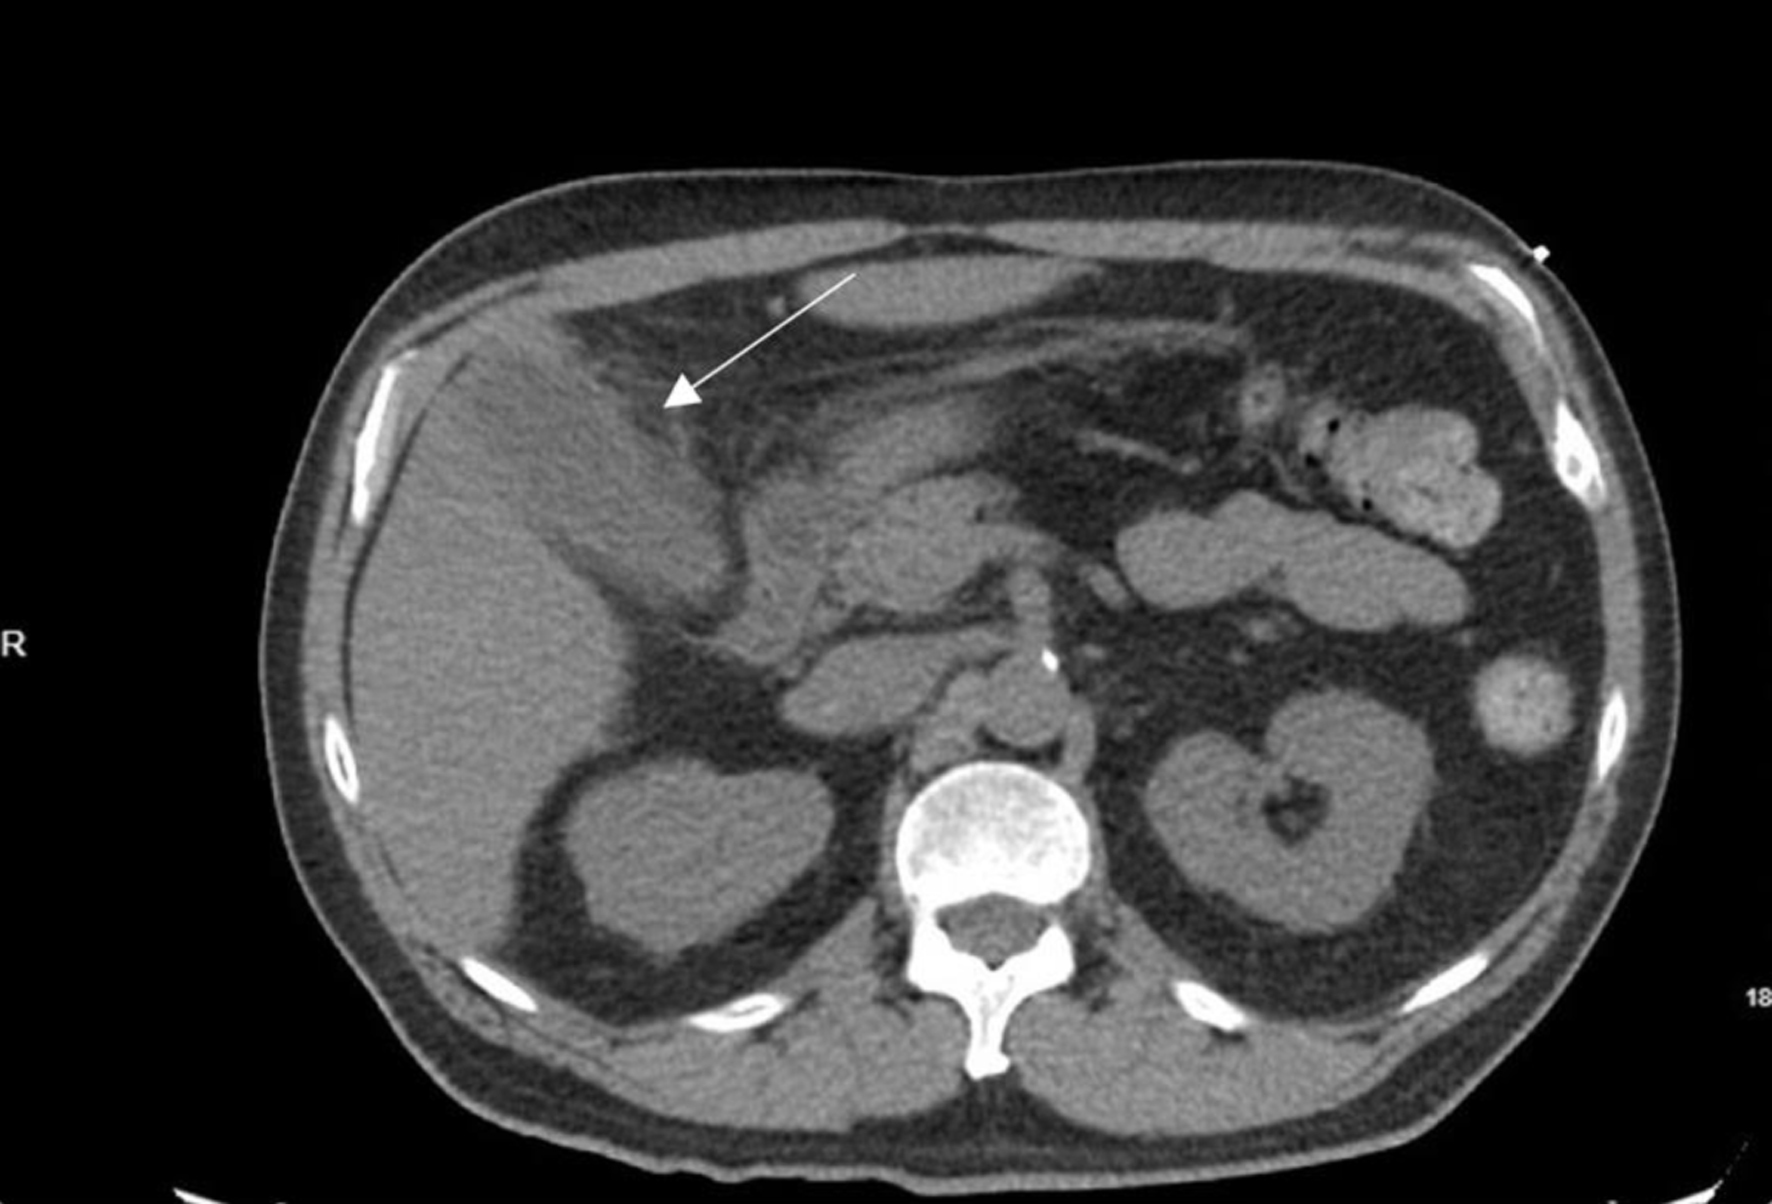

On exam, his abdominal right upper quadrant was non-tender, epigastric area was moderately tender to palpation, and he had a negative Murphy’s sign. Ultrasound showed evidence of gallbladder wall thickening (4.3 mm, normal < 3 mm), non-dilated common bile duct (3.9 mm, normal < 6 mm), gallbladder sludge, and no appreciable gallstones (Fig. 1). Computed tomography (CT) of abdomen and pelvis without contrast showed moderate gallbladder wall thickening with inflammatory changes in the surrounding fat and cholelithiasis (Fig. 2). At this time, labs showed no leukocytosis, non-elevated LFTs, and non-elevated lipase (Table 1). Otherwise, labs were significant for hyperglycemia (glucose 307, reference range 70 - 100 mg/dL) and a calculated anion gap of 19 (reference range 4 - 12 mmol/L) (Table 1). The patient was then admitted for management of DKA.

Click for large image

Figure 2. Axial computed tomography image displaying gallbladder with evidence of moderate gallbladder wall thickening, inflammatory changes in the surrounding fat, and cholelithiasis. Arrow indicates gallbladder with thickened wall.